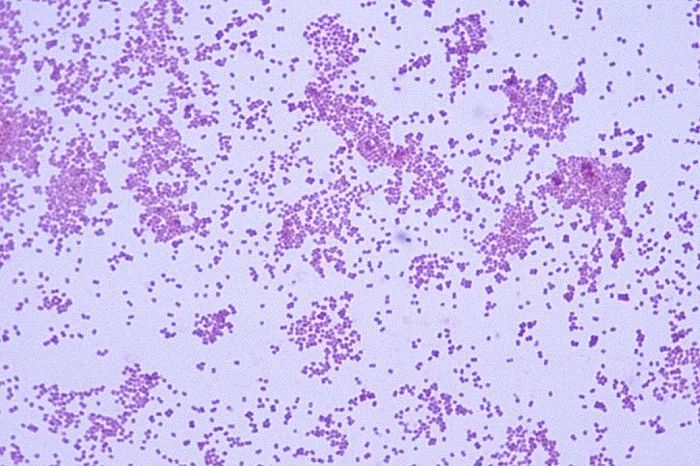

韦荣氏球菌属(Veillonella) 是革兰氏阴性厌氧性微小球菌,直径0.3~0.5μm,初期培植为革兰氏阳性,过夜转为阴性。光学显微镜下为双球状、片状和短链状,无荚膜,无鞭毛,无芽孢。最适生长温度 37℃ ,最适pH6.5~8.0。